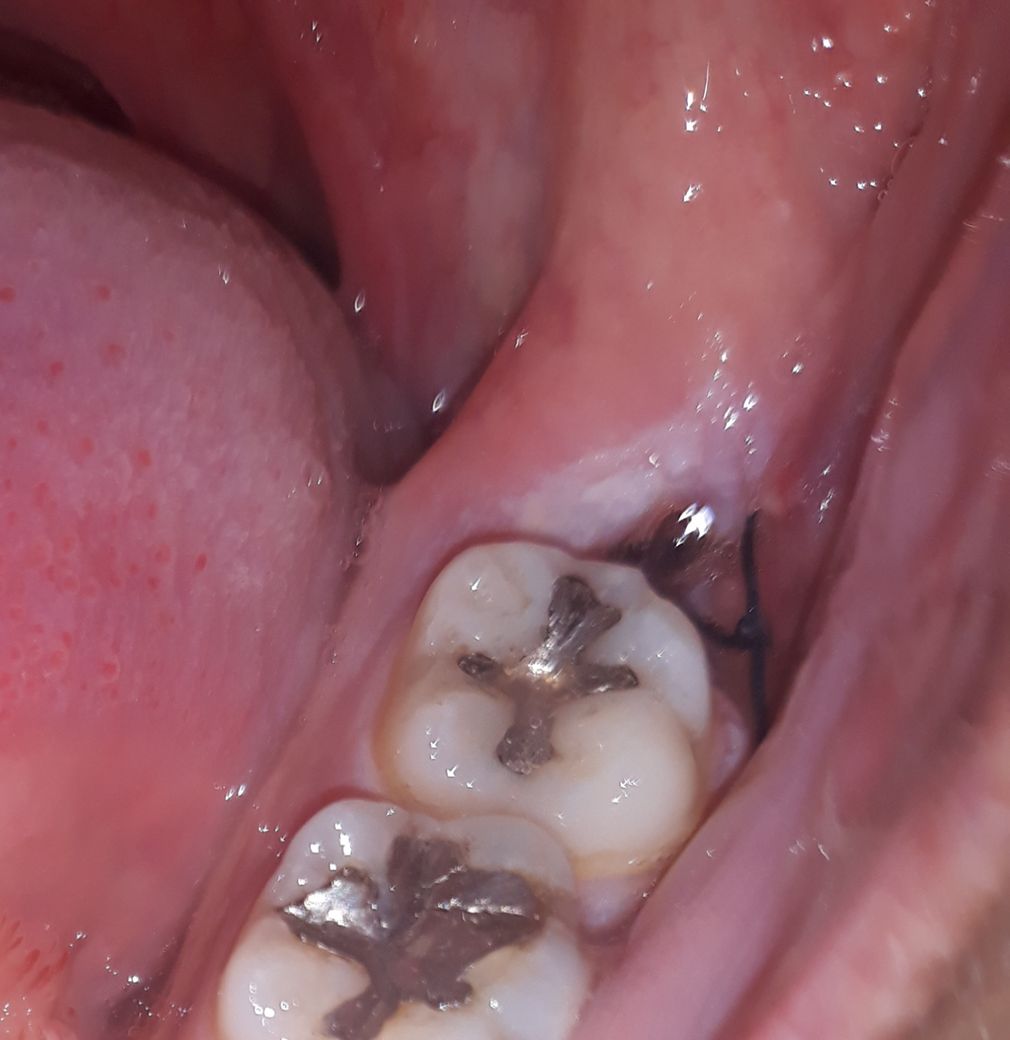

사랑니 발치하고 난 후 이게 피떡이 점점 사라져요

발치하고 최대한 오래 물고 있으라고 해서

4시간동안 묵언수행한다음에 빼서 빨간 피떡같은게 꽉 차있었는데

날이 갈수록 점점 사라져요

• 1번 째 사진

사랑니를 발치한 후 지혈을 하고 생긴 피떡이 계속 유지될 필요는 없습니다. 자연스럽게 소실되어야 하며 올리신 사진으로 정확한 상태를 알 수 없지만 크게 문제될 것은 없어 보입니다.

피떡의 경우 자연스럽게 제거가 되어가는 과정이며, 점차 안에서 살이 차오르면서 빈 공간은 매워질 수 있습니다. 통증지속시 치과에 재내원하여 주시고, 그동안 가글을 꾸준히 하시어 염증방지를 하시는 것이 좋겠습니다.